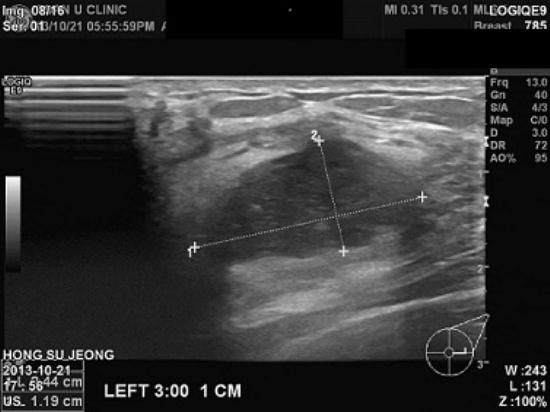

건강검진으로 받은

유방엑스레이상 치밀유방 소견보여 추가로 초음파 검사까지 하시고

검사상 이상소견보여

내원하신

41

여성분이십니다

.

좌측유방에

2cm 넘는 혹이있어 본원에서

조직검사 시행결과 침윤성 유방암으로 진단되셨습니다.